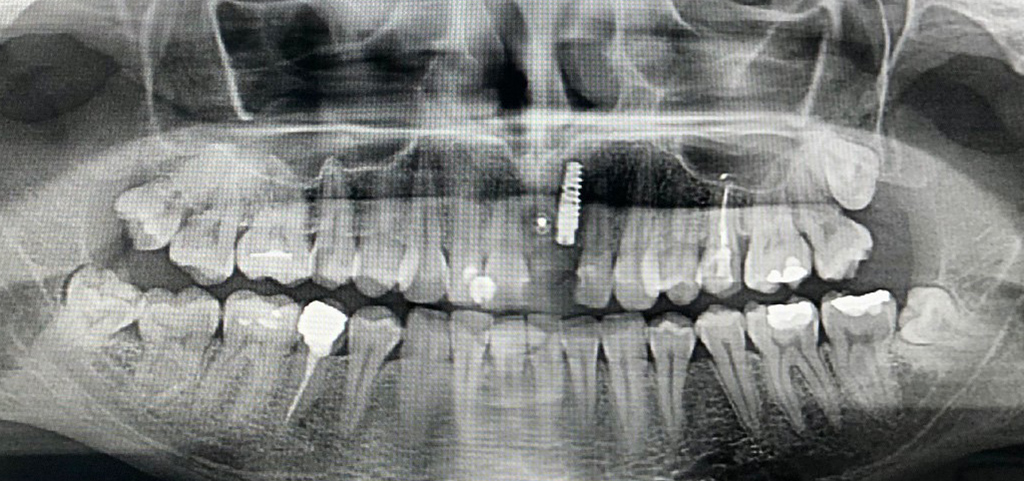

Zdjęcie rtg po zabiegu rekonstrukcji kostnej okolicy górnej lewej jedynki i implantacji

zdjecie rtg po zabiegu rekonstrukcji kostnej

Chirurgia: dr n.med. Ewa Zawiślak